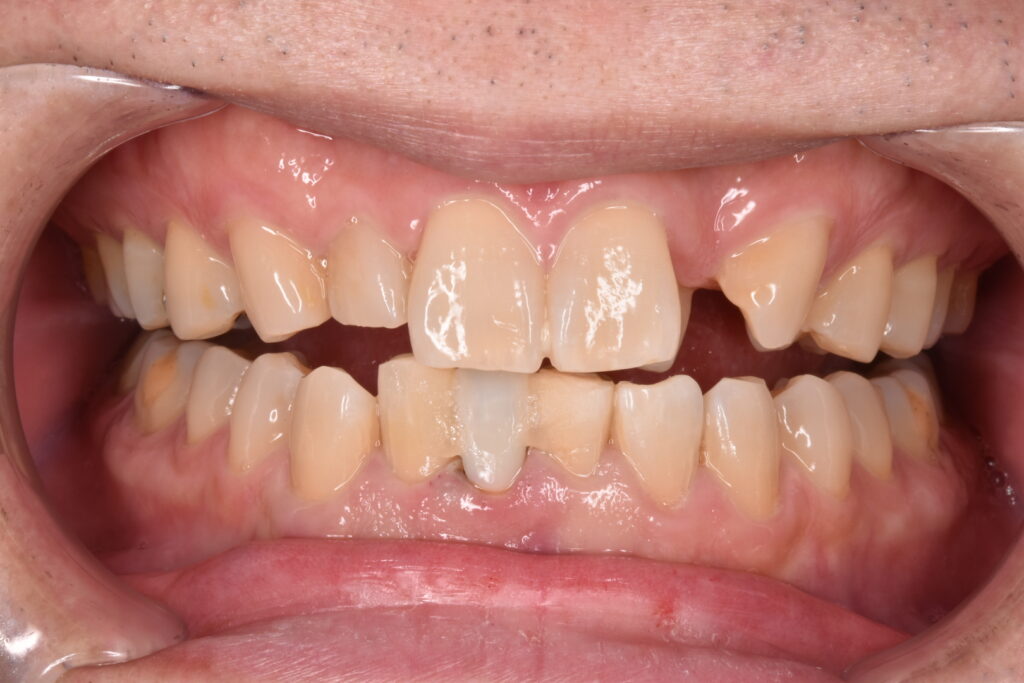

50代男性、1年半前に関東の歯科医院で保険診療で差し歯をやりかえされたそうです。今回その差し歯が取れたとのことで当院にご相談くださいました。診察の結果、土台となるファイバーコアがご自身の歯ごと根本から折れていて、顎の骨ギリギリのところでした。ご本人様とも相談し、今回は自由診療の治療で自分の歯をできるだけ残し、使っていく方針で固まりました。

右下の前歯が差し歯でした。根本から折れていて一部が歯ぐきの中3ミリ近くに達しています。この破折縁から骨までは1ミリもなくこのままセラミックを被せても予後が悪いと説明させて頂きました。